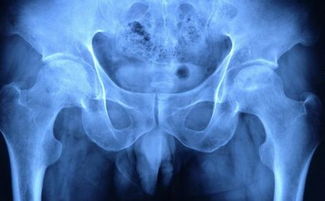

兒童股骨頭壞死屬于無(wú)菌性軟骨病,其形成的原因可能是股骨頭骺缺血壞死,從而影響兒童股骨頭內軟骨,其病因尚不明確,專(zhuān)家推測過(guò)這幾種可能。

第一,目前為止,在血管學(xué)說(shuō)方面的研究較多,它和成人股骨頭壞死的發(fā)病有類(lèi)似之處,其股骨頭頸內靜脈回流出現障礙,導致骨內壓增高致動(dòng)脈缺血,引起股骨頭壞死。

第二,關(guān)節內壓增高,凡是能導致髖關(guān)節內壓增高的因素,如外傷性關(guān)節積血、暫時(shí)性滑膜炎,會(huì )影響關(guān)節滑液循環(huán)額伸髖內旋等非生理體位,均有可能造成關(guān)節內增高。

第三,孩童身體還在成長(cháng)中,身體部位較為脆弱。反復微骨折在股骨頭骨松質(zhì)網(wǎng)狀結構較為脆弱,易引起反復微小骨折?;顫姁?ài)動(dòng)的孩童,比較多發(fā),易常見(jiàn)到微小骨折。

第四,孩童骨發(fā)育異常,遲緩。骨發(fā)育遲緩,男孩骨齡減慢者占74%,女孩骨齡減慢者22%。以及一些其他因素如血凝障礙疾病、血液黏稠度增加、血管病變等。

以上就是會(huì )引起兒童股骨頭壞死的幾種可能性,兒童較為脆弱,家長(cháng)們一定要多加注意。如果真的有出現股骨頭壞死的可能性,應立即及時(shí)就診。